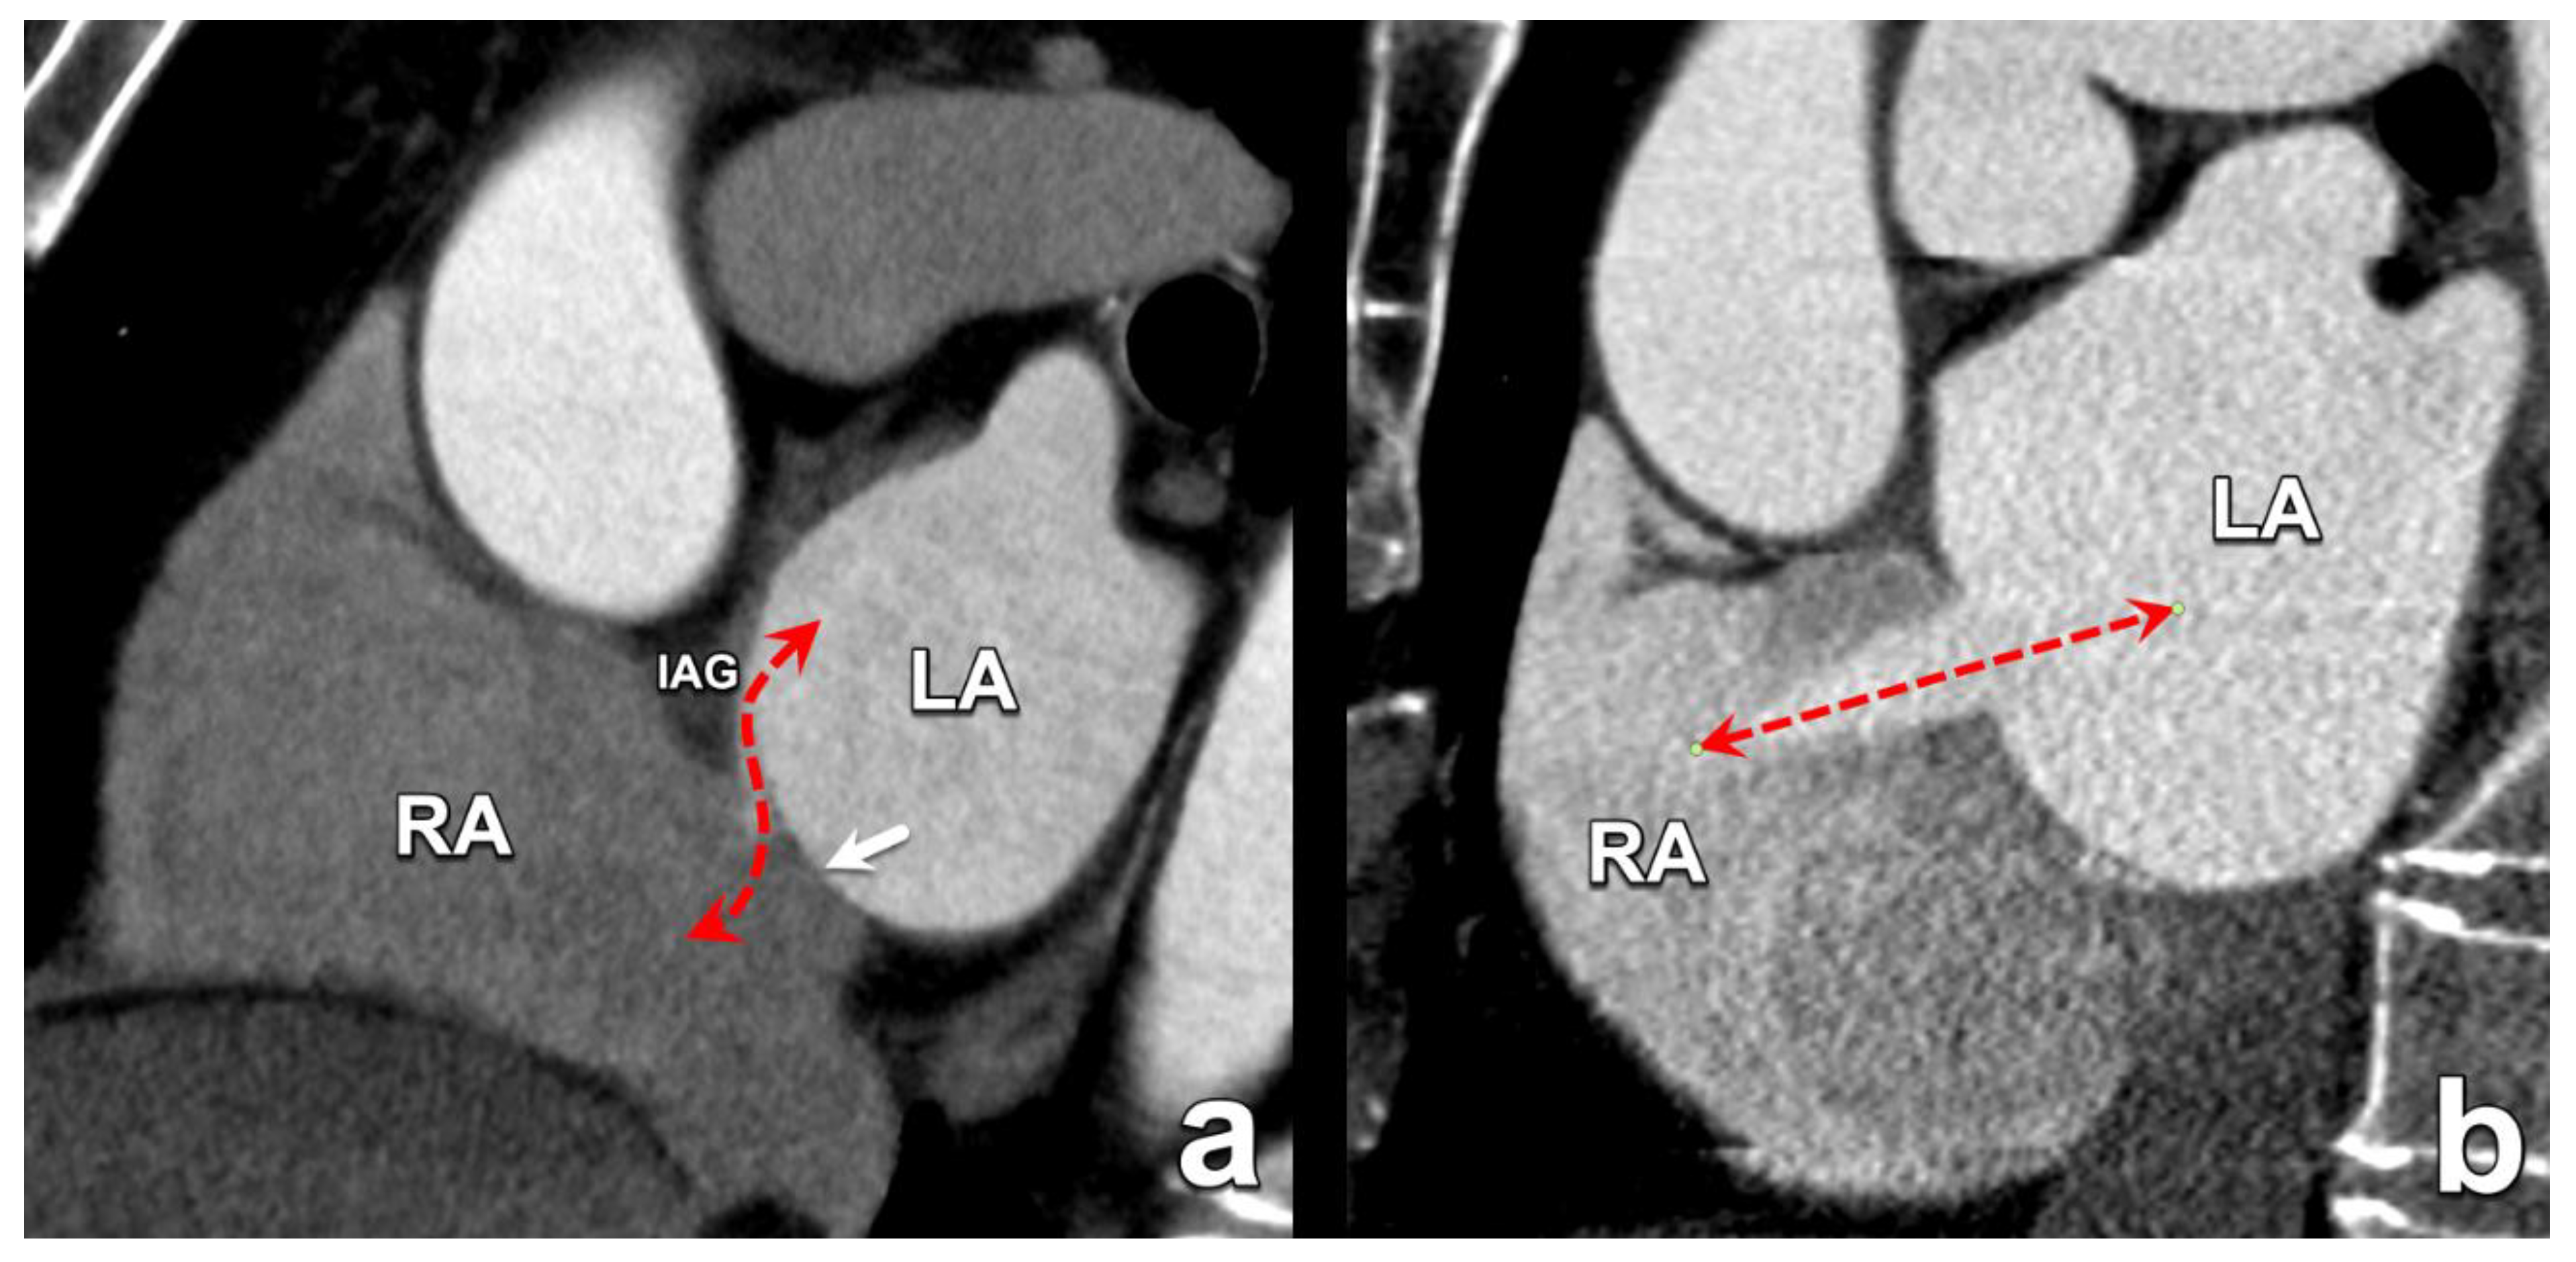

2. Atrial Septal Defects